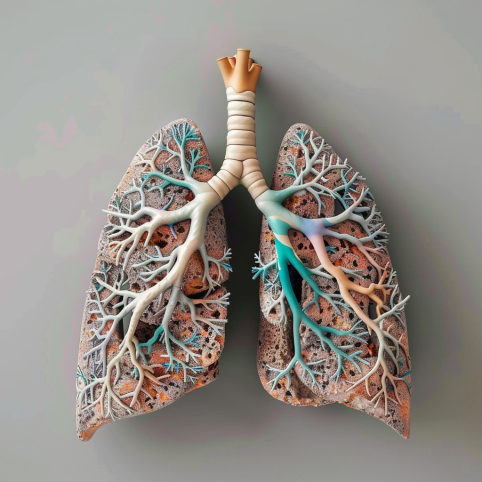

Jaki to konflikt:

Konflikt lęku przed śmiercią, złości i braku radości życia